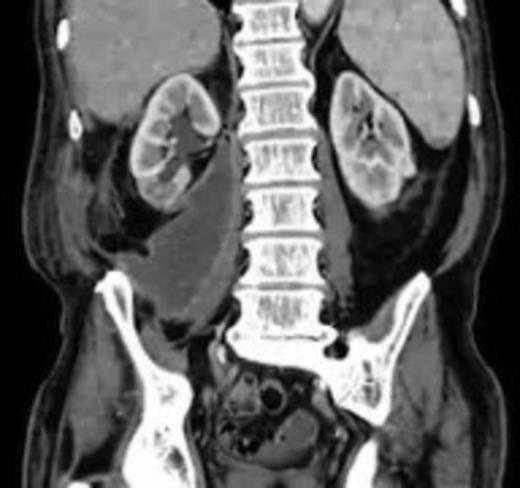

The patient's condition improved quite rapidly and the intravenous antibiotics were stopped and replaced with oral ciprofloxacin upon microbiological advice (for a total of six weeks). The drain was removed after 2 weeks when the series of repeat CT scans showed the abscess had nearly completely resolved (Fig. 5). Further CTs on follow up at 6 weeks and 3 months post discharge show no collection at all. At the last clinic visit 6 months following his last admission the patient was enjoying good health.

Near complete resolution of psoas collection after 2 weeks of intravenous antibiotics